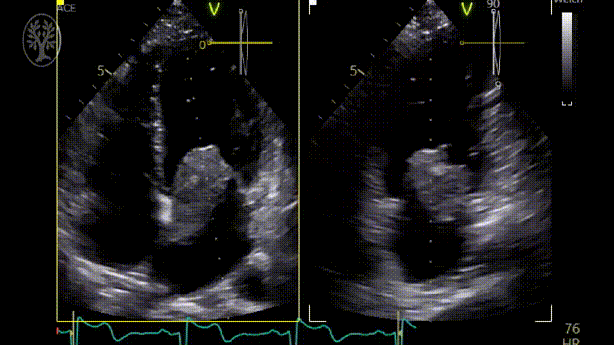

患者入院时血压正常(114/65mmHg),心律规整(76次/分钟),心脏听诊无杂音,无心力衰竭迹象和局灶性神经功能缺损。双侧股动脉和桡动脉搏动可触及,但双侧胫后动脉和足背动脉搏动消失。踝肱比(ABI)右侧为0.9,左侧为0.8。心电图示P波双相,经胸超声心动图显示LVEF正常,无室壁运动异常,左心房内有一个较大占位(5.1×2.5×2.8cm),通过二尖瓣进入左心室,导致中度二尖瓣狭窄(视频1,视频2)。

胸部CT示左心房内有蒂肿块,通过二尖瓣突出到左心室(图1)。下肢超声显示双侧腘动脉血栓形成,但双侧肢体仍通过侧支循环保持灌注。

图1.CT示左心房内有蒂肿块